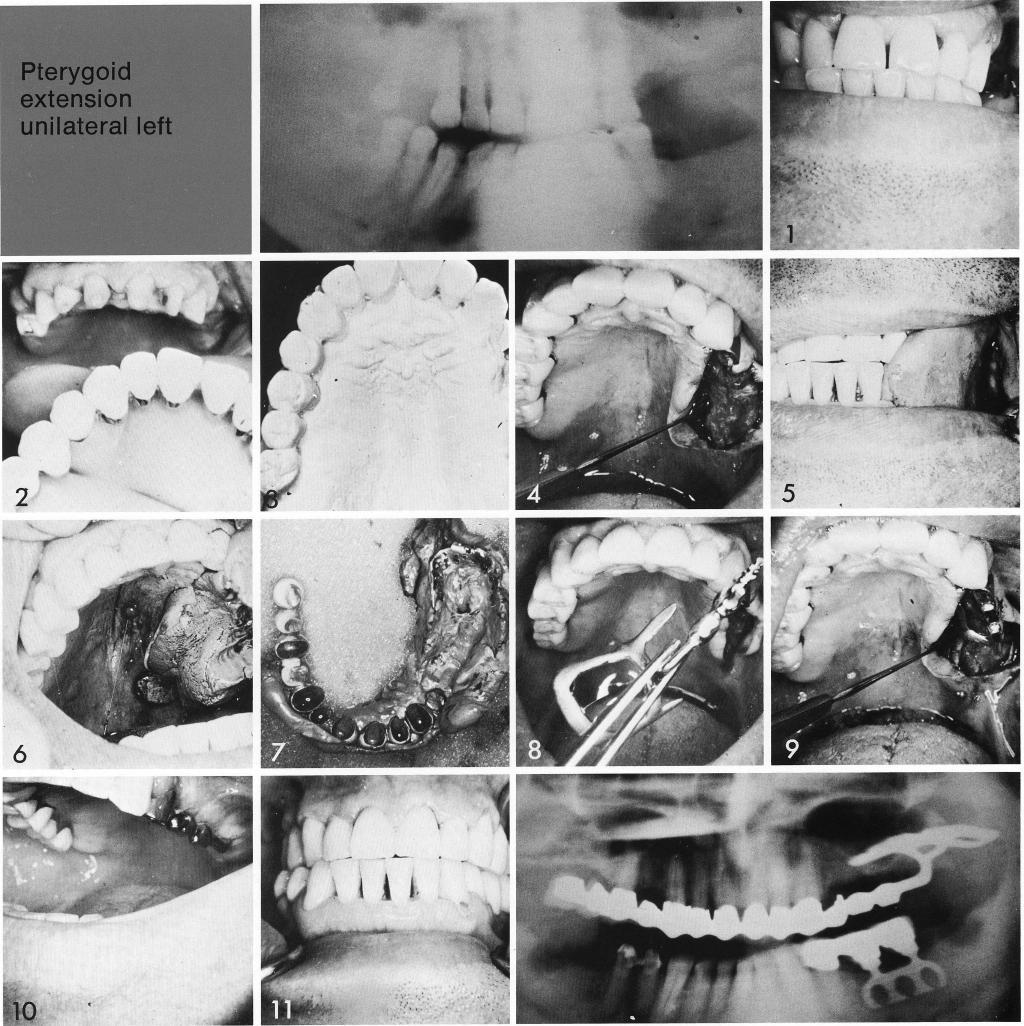

Pterygoid extension

unilateral left

A three-quarter arch restoration is made for the remaining teeth (1,2). As always before bone surgery, a full mouth soft tissue impression is taken to measure tissue thickness in the edentulous area so that the pterygoid implant pontics will not impinge or interfere with the occlusion. The unilateral posterior edentulous site was then revealed (3). The prototype was inserted and an impression made (4,5), which picked up the prototype as well as the restoration (6). On the stone model (7), the implant was designed. The implant was inserted (8,9), and after the site healed (10), impressions were taken for the final splint.

1 Three quarter maxillary arch restoration made for the remaining teeth